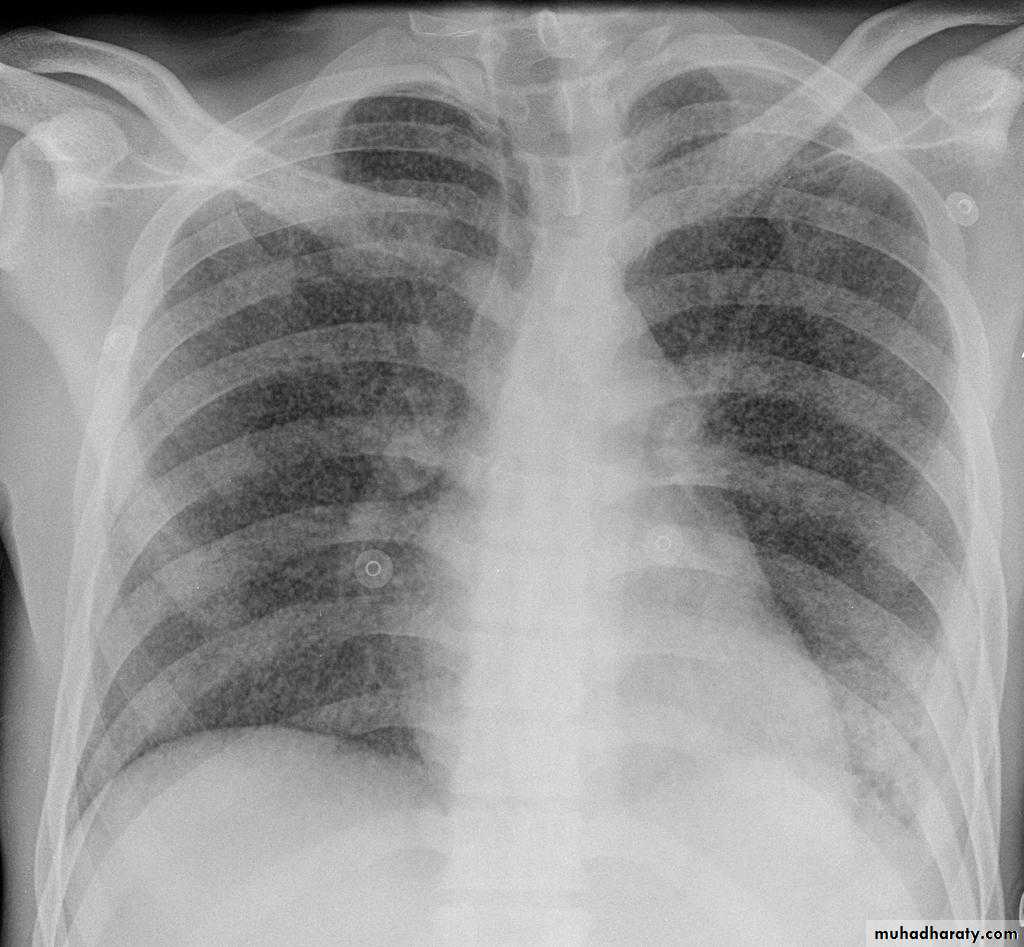

Pulmonary emphysema

Pulmonary emphysema is defined as the "abnormal permanent enlargement of the airspaces distal to the terminal bronchioles accompanied by destruction of the alveolar wall and without obvious fibrosis". Emphysema is one of the entities grouped together as chronic obstructive pulmonary diseaseRadiographic features

Plain filmExcept in the case of very advanced disease with bulla formation, chest radiography does not image emphysema directly, but rather infers the diagnosis due to associated features :

hyperinflation:

1.flattened hemidiaphragm(s): most reliable sign

2.ncreased and usually irregular radiolucency of the lungs

3.increased retrosternal airspace

4.increased antero-posterior diameter of chest

5.widely spaced ribs

6.sternal bowing

7.tenting of the diaphragm

8.saber-sheath trachea

9.vascular changes paucity of blood vessels ( absent pulmonary markings in outer 1/3 of the lung fields )

10 .pulmonary arterial hypertension

pruning of peripheral vessels

increased calibre of central arteries

right ventricular enlargement